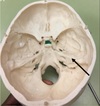

1. Identify the structure. 2. What structures traverse this canal

1. Foramen Rotundum 2. Maxilliary nerve, V2 off trigeminal M.R Triangle R.O.S.L

115

1. Identify the structure. 2. What structure traverses this canal?

1. Superior Orbital Fissure 2. CN3,4,5 V1 off trigeminal, opthalmic artery

116

1. Foramen Spinosum 2. Middle Meningeal Artery, Meningeal branch of Mandibular Nerve Foramen Ovale (red arrow) Accessory Meningeal Artery, v3 c5 Mandibular Nerve, Lesser Superficial Vitrosal nerve, Emissiary nerve

117

1. Foramen Lacerum 2. The artery of pterygoid canal, the nerve of pterygoid canal. Internal carotid runs superiorly not through.